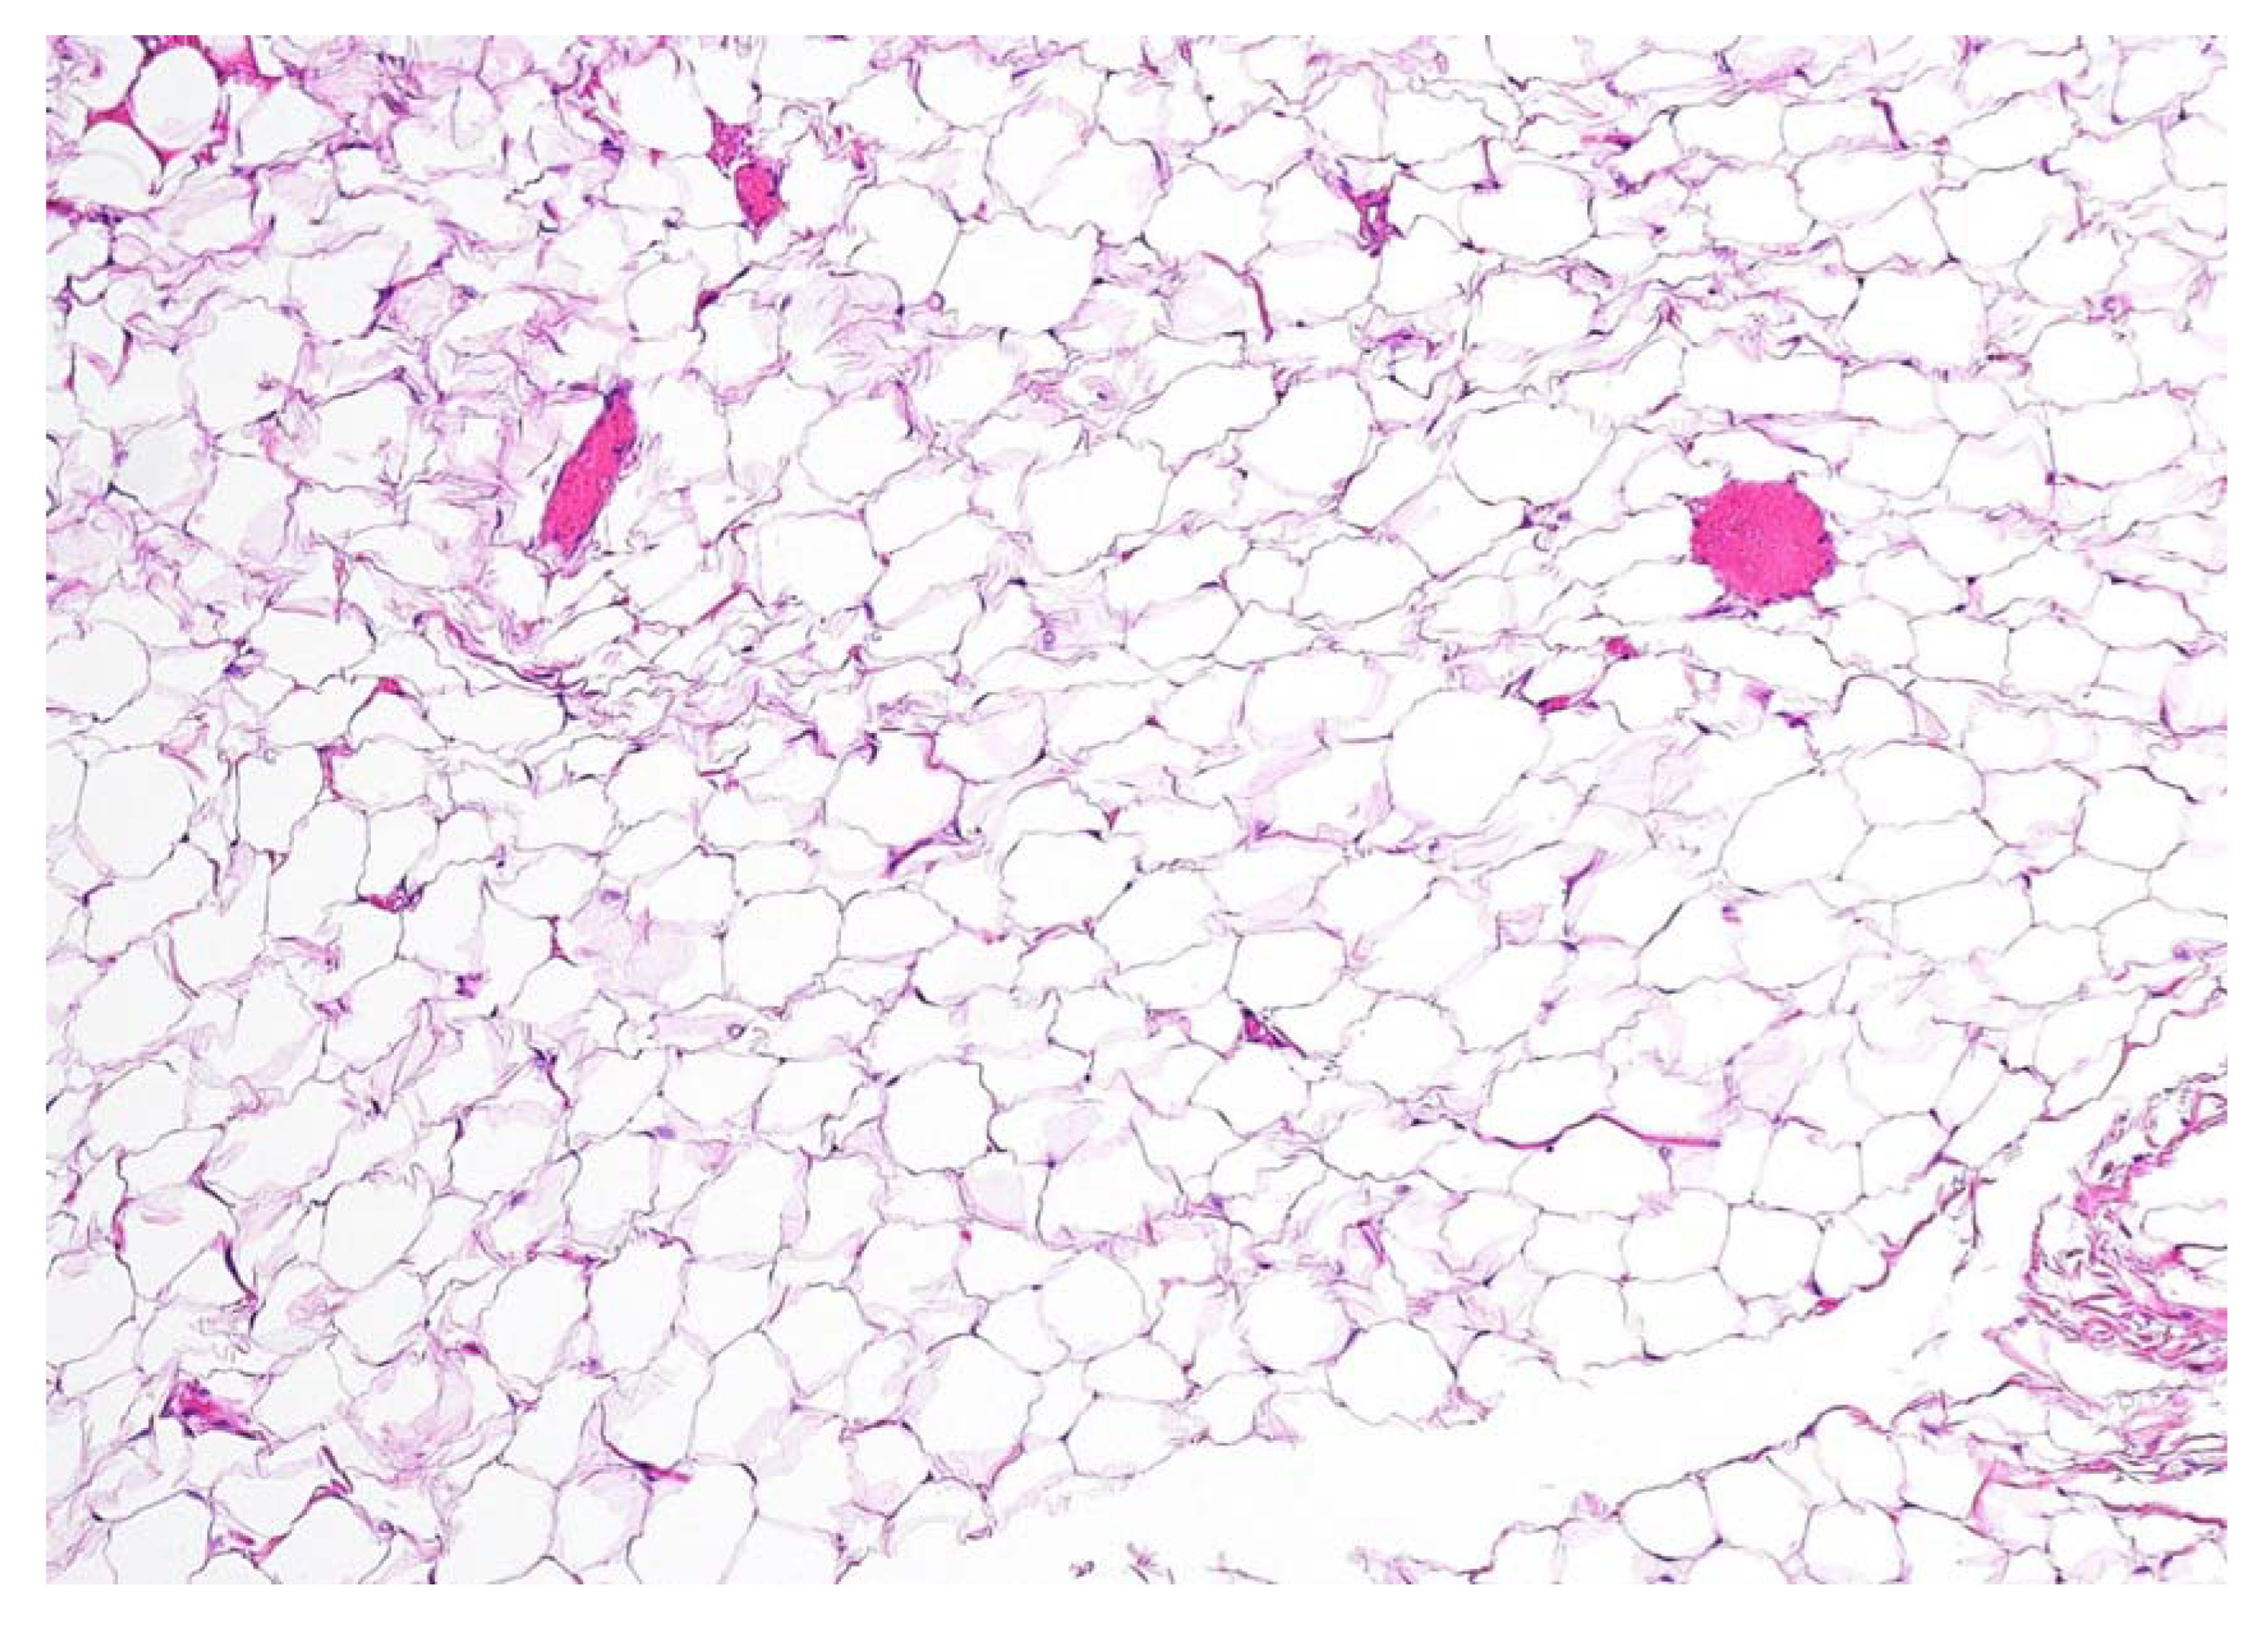

Figure 4.

Definitive histopathological examination of the specimen confirmed the hypothesis of an encapsulated lipoma composed of simple adipose cells with no atypia present. In the present picture a 10× microscopic view of a formalin-fixed paraffin-embedded section of the lesion is shown, stained with hematoxylin-eosin. No thyroid remnants were apparent in all of the examined sections. No swallowing alterations were reported at a follow-up of 6 months after the operation, nor was there any clinical and ultrasonographic evidence of disease recurrence.